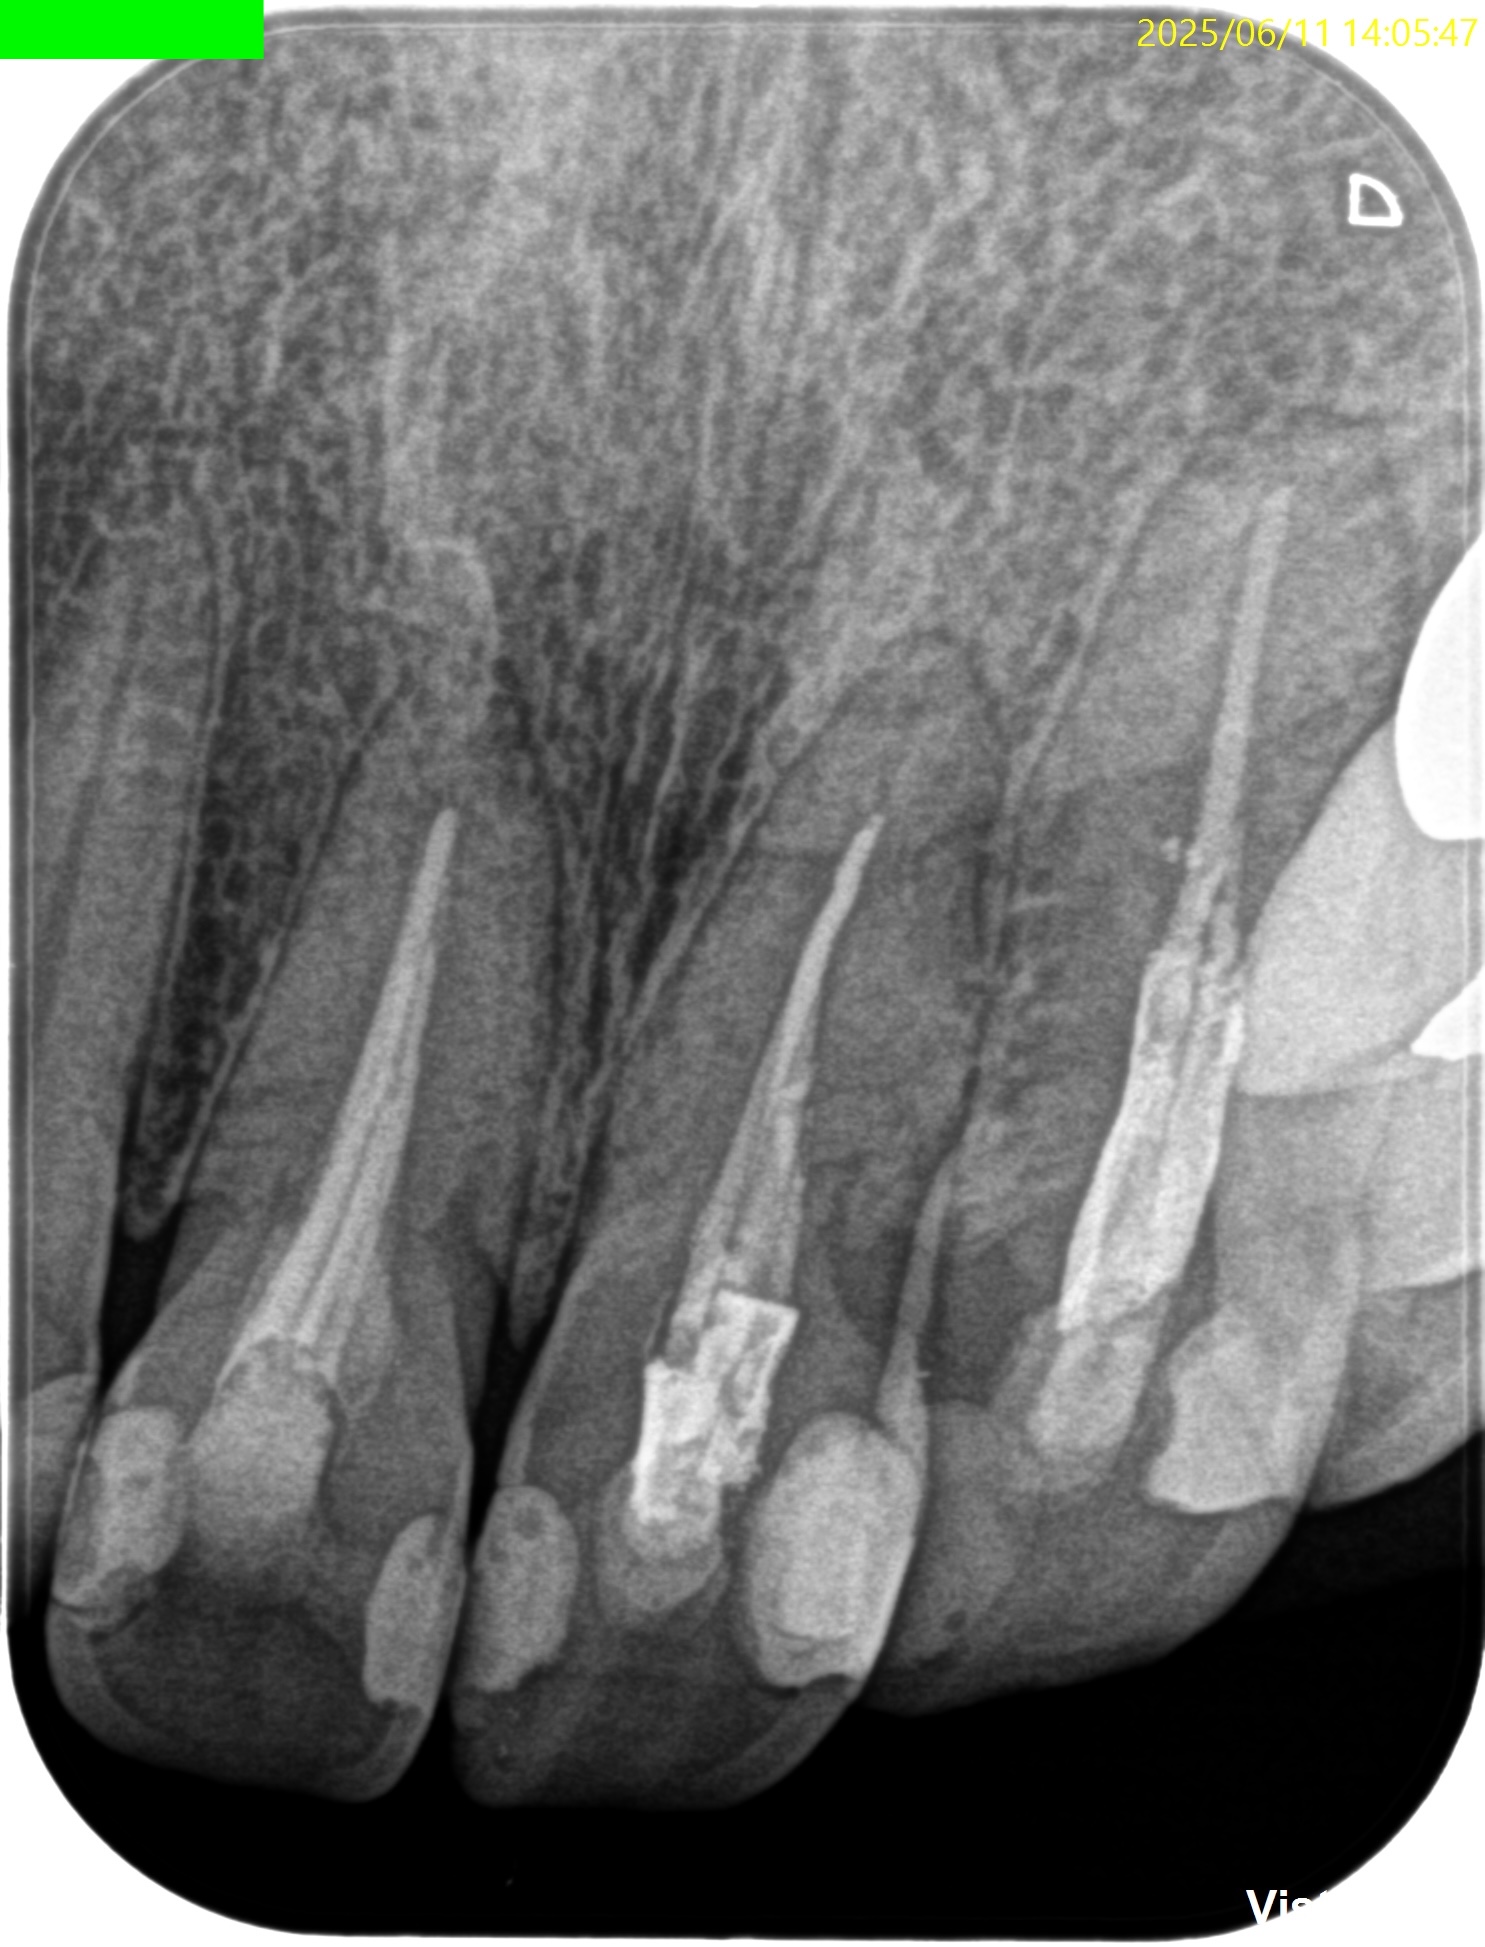

PA(2025.6.3)

#8,9,10ともに全く根管治療が不適切としか言いようがない。

#8はForamen付近の形成が太そうだ。